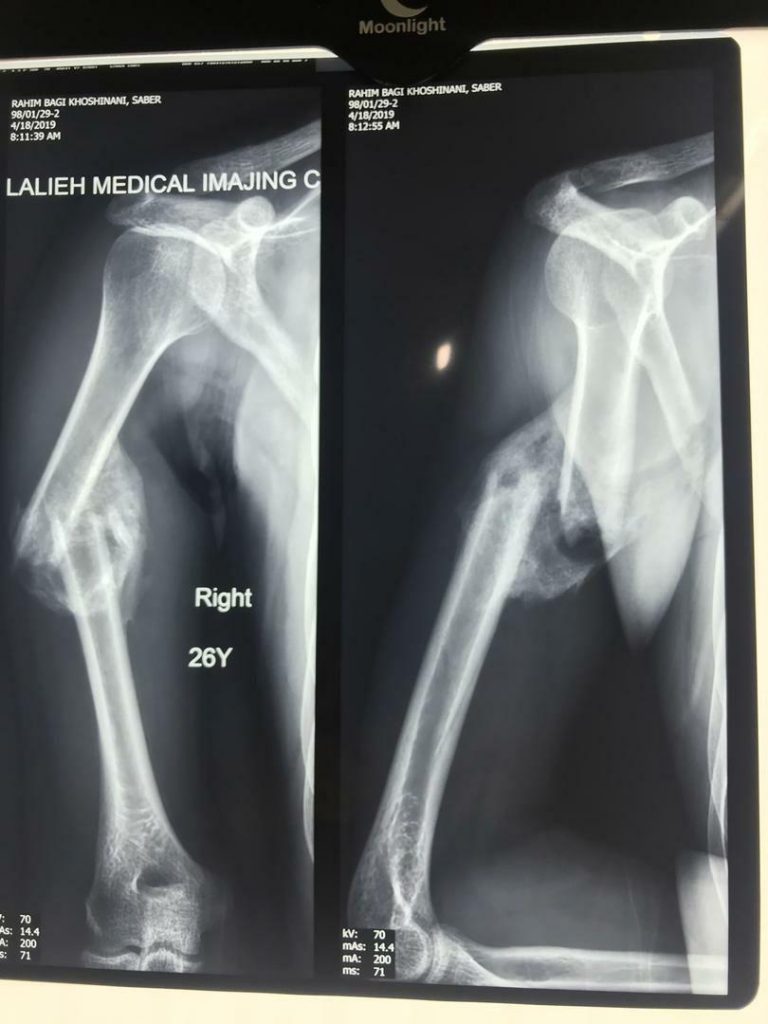

جراح ارتوپدی و شکستگی

3. شکستگی و دررفتگی استخوان

درصورتی که شدت آسیب وارد شده به مفصل به گونه‌ای باشد که با سایر روش‌های درمانی آسیب برطرف نشود، جراح ارتوپد عمل تعویض مفصل را برای درمان توصیه می‌کند. با این عمل، بخشی یا همه محل آسیب دیده مفصل با پروتز جایگزین می‌شود. عمل تعویض مفصل به طرز قابل توجهی درد مفاصل آسیب دیده را کاهش می‌دهد، موجب بهبود توانایی حرکتی مفصل و کاهش مشکلات حرکتی فرد و به طور کلی باعث بهبود کیفیت زندگی فرد می‌شود.